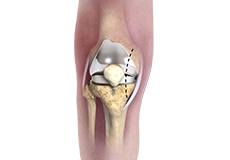

Unicompartmental/Partial Knee Replacement

Unicompartmental knee replacement is a minimally invasive surgery in which only the damaged compartment of the knee is replaced with an implant. It is also called a partial knee replacement.